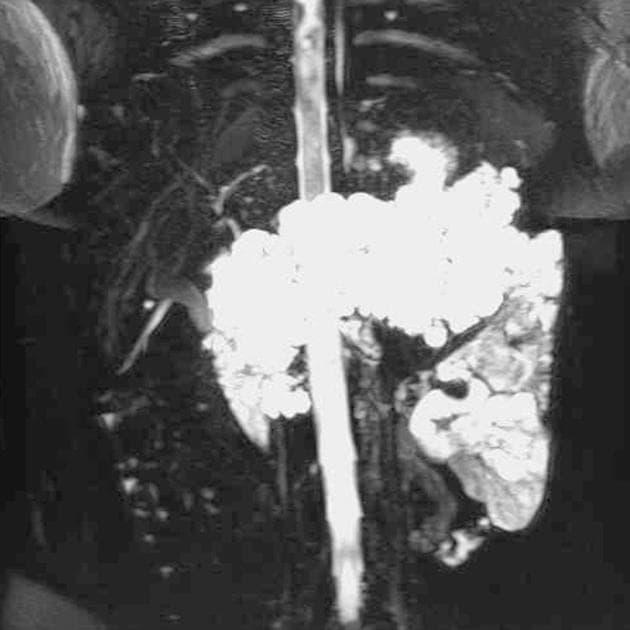

- Nhiều nang thận đơn thuần cũng như nhiều u thận tổn thương hỗn hợp đặc - nang.

- Tuyến tụy cũng chứa một số lượng rất lớn các nang rải rác khắp nơi.

Ca lâm sàng này biểu hiện đầy đủ các đặc điểm của hội chứng Von Hippel-Lindau (VHL), bao gồm nhiều nang thận đơn thuần và nhiều u thận tổn thương hỗn hợp đặc - nang. Tuyến tụy cũng có rất nhiều nang lan tỏa.